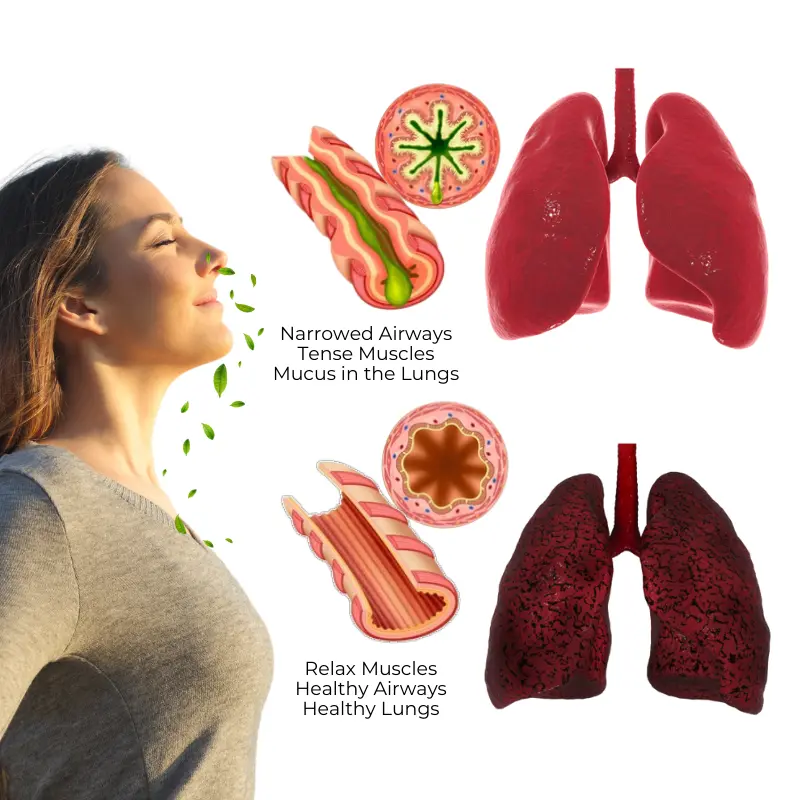

How Biancat® RespiCleanse Works to Restore Your Lung Health

Biancat® RespiCleanse combines nature and innovation. Using advanced herbal technology, its active ingredients penetrate deep into your airways to liquefy and expel lung mucus, detoxify your respiratory tract, and support lasting lung health. Organic extracts like mullein and licorice work synergistically to create a protective barrier, reducing inflammation and preventing infection.

- Ease Respiratory Discomfort – Effectively calm nagging coughs and reduce irritation, while clearing built-up mucus to open your airways and restore smooth, natural breathing for improved comfort and relaxation.